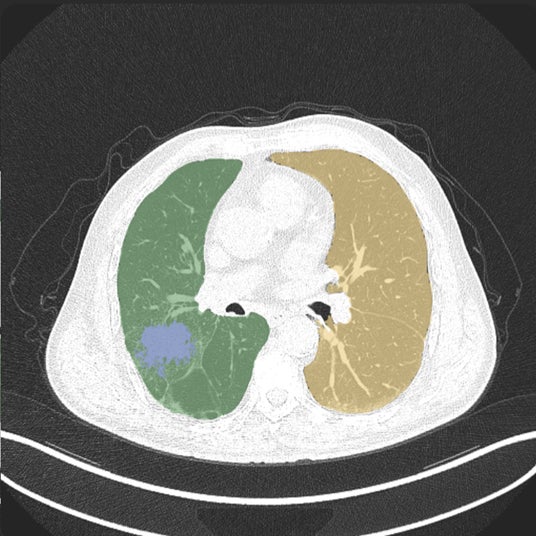

無料配布中の肺がんCTデータセット

Callisto DataHubのリリースを記念して、正解付き(肺がんと肺野のセグメンテーション)の152症例の肺がんCTデータセットを無料配布しています。このデータセットは、The Cancer Imaging Archiveに公開されている「Lung-PET-CT-Dx」データセットに放射線科専門医がアノテーションとダブルチェックを施したものです。腺がん・小細胞がん・扁平上皮がん・大細胞がんなど、様々な肺がんタイプを網羅した、この高品質なアノテーション付きデータセットは、医療AI・創薬AI・臨床試験などの研究開発に利用できます。このデータセットが役に立ちましたら、DataHub上の他の医用画像データセットの購入も検討していただければ幸いです。